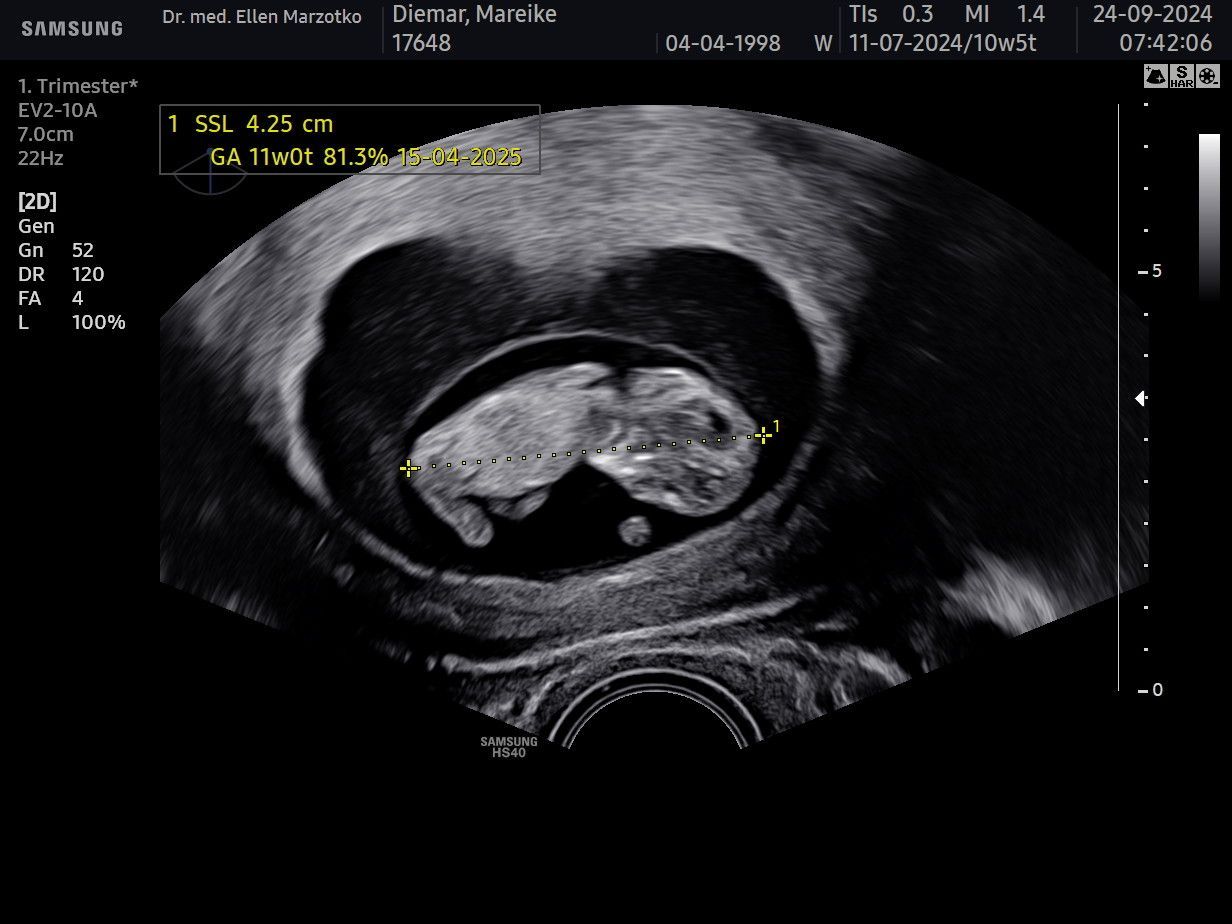

Am 24.09.2024 haben wir dich endlich wieder sehen können. Da warst du gerade mal 4 cm groß und ich in der 11. SSW.